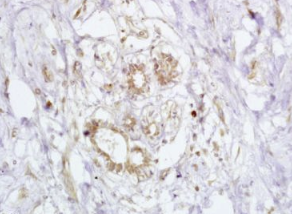

组织/细胞:人乳腺癌;4%多聚甲醛固定石蜡包埋;

抗原提取:柠檬酸缓冲液(0.01M,pH 6),15min煮沸,用3%过氧化氢阻断内源性过氧化物酶30min;37℃下阻断缓冲液(正常山羊血清)20 min;

孵育:抗-BRCA2/FANCB多克隆抗体,未结合1:200,在4°C下过夜,然后与二级抗体结合,DAB染色。